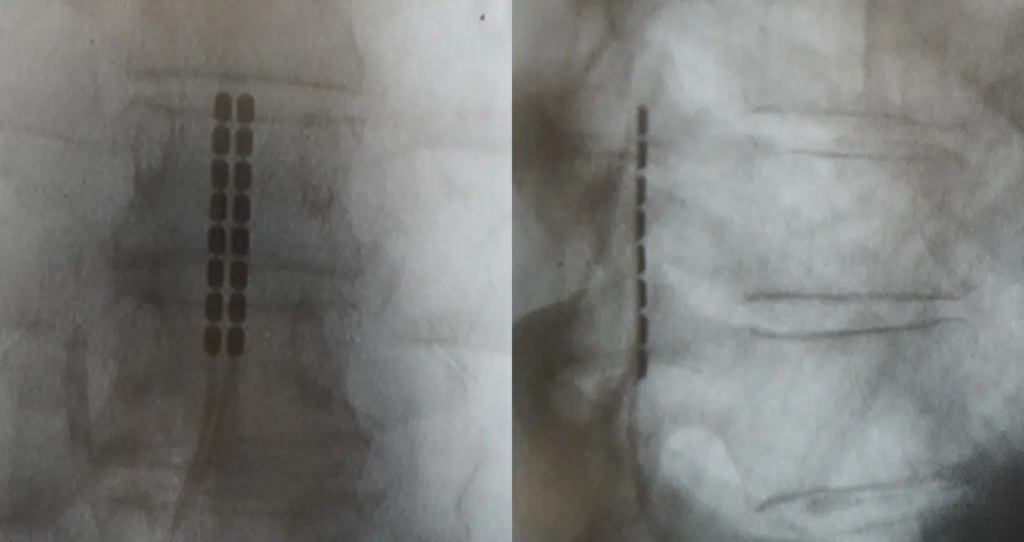

Spinal cord stimulation (SCS) is a revolutionary step in managing chronic pain. In this procedure, the doctor places a stimulating electrode on the spinal cord. The aim is to block the pain signals from reaching the brain.

Before the surgery, the patient goes through a trial. This involves the placement of a wire(s) and controlling it externally. With this test, the patient and doctor can determine if the electrical pulse aids in masking the pain signal.

Upon a successful trial, surgery will take place to insert a permanent stimulator. Here, an incision is made on the back and near the waist. The doctor will place a paddle with electrodes in the space behind the spinal cord, the wires are then tunneled under the skin to the waist and connected to a battery-powered generator at the waist.